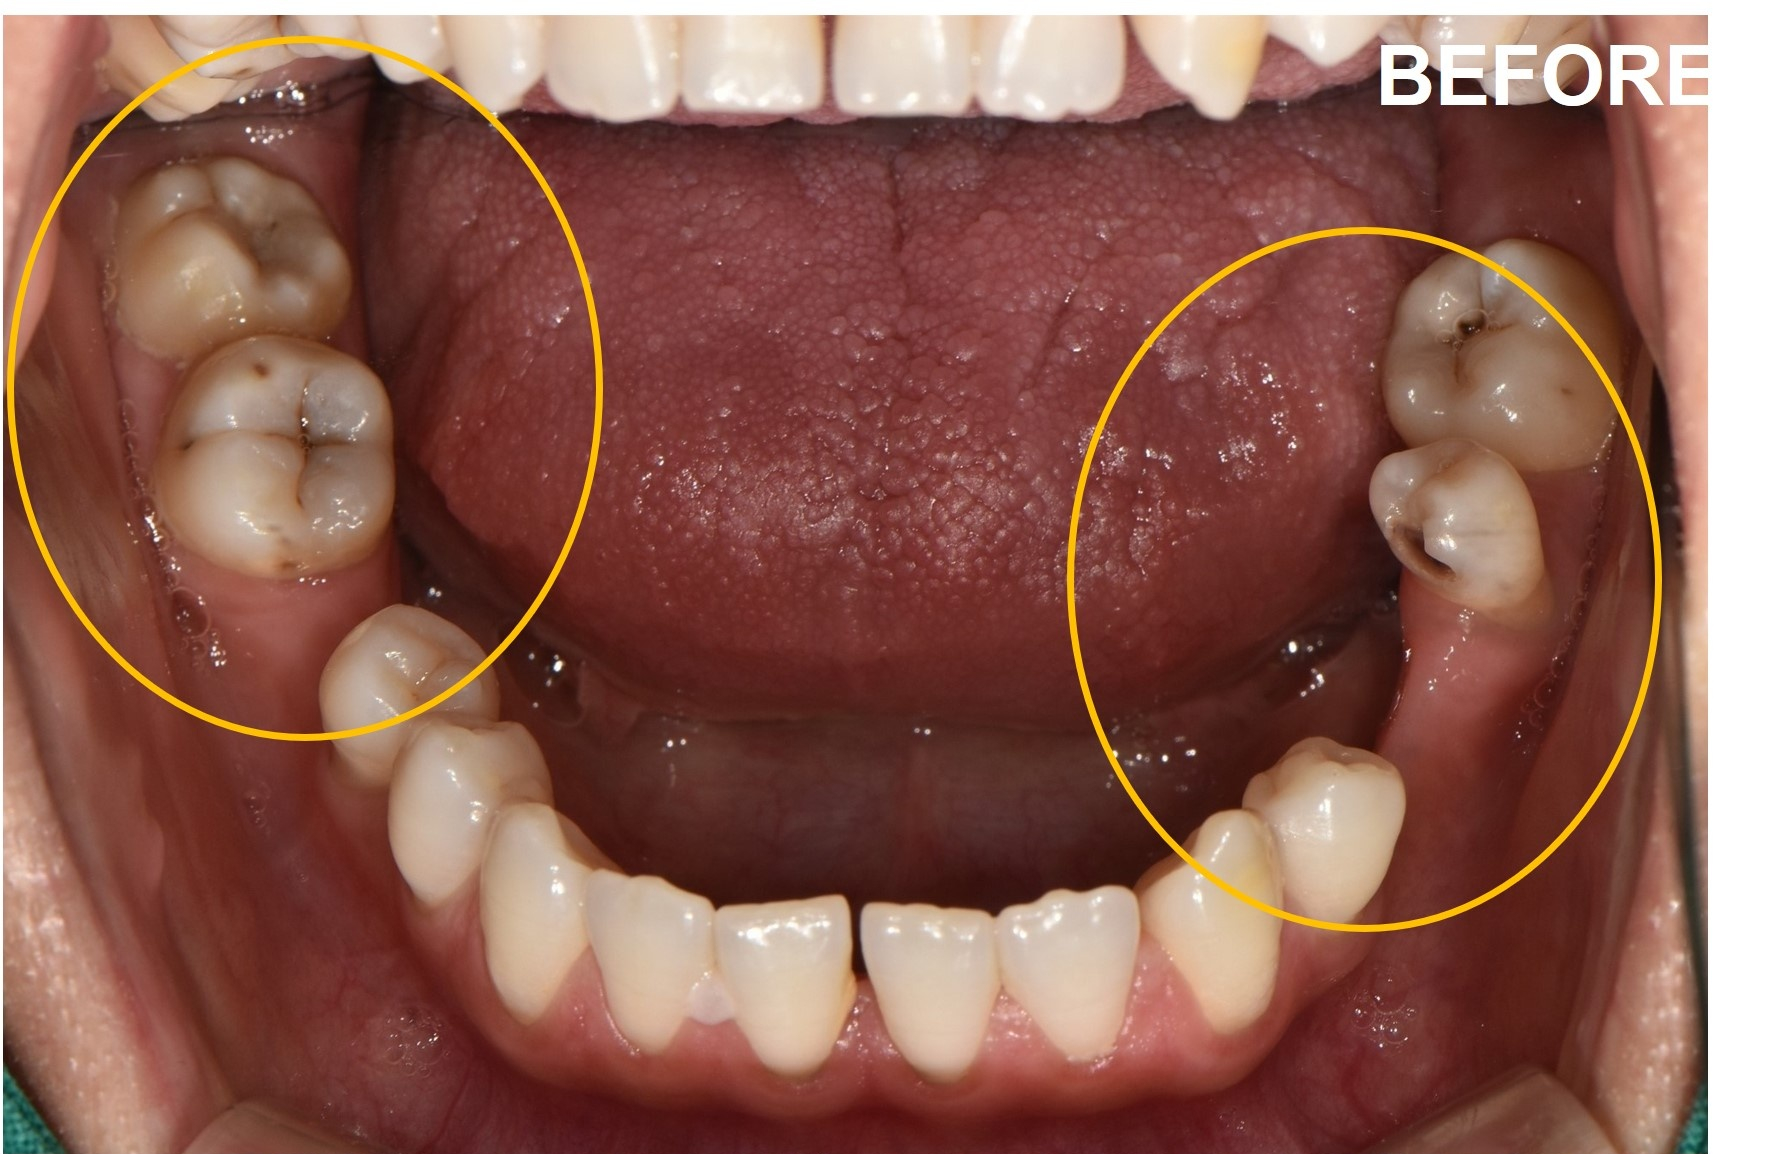

환자분은 양쪽 아래 어금니가 없었습니다.

선천적 무치아증으로 태어나서 어금니가 없었고, 10년 넘게 그렇게 지내왔다고 말씀하셨습니다.

구강 검진 결과는 예상보다 심각했습니다.

어금니가 없는 공간을 메우려는 듯 양쪽 치아가 서서히 쏠리고 있었습니다.

또한 턱관절은 불균형을 이루고 있었고, 전체적인 교합은 이미 무너진 상태였습니다.

비포 사진과 애프터 사진을 나란히 놓고 보니, 단순히 치아가 생긴 것 이상의 변화가 보였습니다.

쏠렸던 치아들은 제자리로 돌아갔고, 교합 평면은 균형을 이루었으며, 양쪽 어금니가 동시에 닿으면서 턱관절의 부담도 줄어들었습니다.